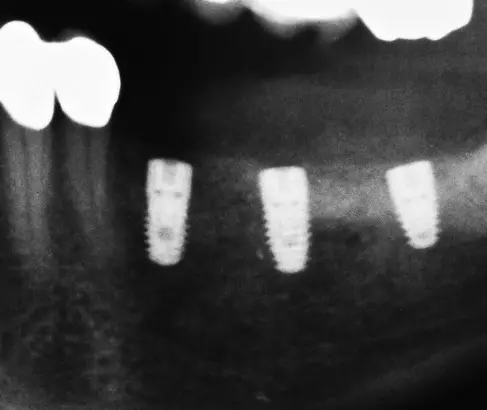

Nach 6 Monaten Einheilzeit wurde die Gitterentfernung mit gleichzeitiger Implantation durchgeführt. Nach Vorbereiten der Patientin und entsprechender Lokalanästhesie wurde eine marginale, entlang an Zahn 34 und der vorhandenen Narbe krestale leicht linguale Schnittführung gewählt. Zur Darstellung des Gitters wurde ein vestibulärer und lingualer Mukoperiostlappen präpariert. Das Gitter zeigte sich regelrecht eingeheilt und zum Teil sogar knöchern bedeckt (Abb. 28). Zur Entfernung des Gitters wurde dieses an der mittleren Sollbruchstelle aufgebrochen und der linguale und vestibuläre Anteil getrennt entfernt (Abb. 29a und b). Anschließend wurde das Implantatlager vorgebohrt und entsprechend dem Bohrprotokoll des Herstellers aufbereitet (Abb. 30). Der Planung folgend wurden dann drei Implantate (Bego SC) regio 35 mit 4,1 x 8,5 mm, regio 36 mit 4,5 x 8,5 mm und regio 37 mit 4,5 x 7mm gesetzt (Abb. 31). Für eine Nachkorrektur der Knochenkontur um die gesetzten Implantate wurde nochmals DBBM eingebracht, mit einer Kollagenmembran (Geistlich Bio-Gide) und PRF abgedeckt und mit einer spannungsfreien Naht verschlossen (Abb. 32 und 33). Das postoperative Röntgenbild zeigt die drei gesetzten Implantate (BEGO SC) an den jeweils vorher digital geplanten Implantatpositionen (Abb. 34).

Praxis Dr. Dr. Tröltzsch